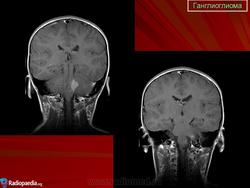

Ганглиоглиома — бифракционная опухоль, состоящая из элементов ганглиоцитомы и пилоцитарной астроцитомы. Локализуется преимущественно в полушариях головного мозга. Макроскопически представляет собой плотную четко отграниченную от ткани мозга опухоль, которая нередко содержит кисту.

Ганглиоглиома